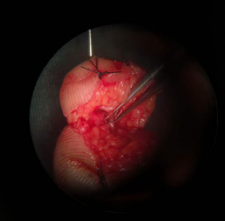

术中吻合血管情况,血管管径仅有0.3mm

唐洪伟医生说:这个手术难度比较大,令人头疼。主要是血管太细,不容易找到,找到以后,需要非常高的显微外科技术,可能很多人一看这种情况,就直接放弃再植手术了。还有就是患者高血压、糖尿病多年,血管有不同程度的硬化,弹性差,影响术后成活,同时也面临着万一不成话,还需要二次手术等心理压力,不过看着病人,对我信任的眼神和殷切的希望,我还是决定立即行再植手术。现在患者手术成功,功能正常,手指活动非常灵活,非常满意。